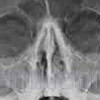

Рентгенография костей носа

Рентгенография костей носа. Исследование костного основания носа и соседних структур лицевого черепа с помощью рентгеновского излучения. Используется для просмотра костей и пазух. Используется при диагностике переломов, для подтверждения инфекционных и воспалительных процессов. Назван для выявления злокачественных опухолей, полипов и кист. Поскольку исследование затрагивает околоносовые пазухи, процедура может использоваться для определения их легкости. Рентгенография костей носа проводится при подозрении на присутствие инородных тел, а также при подготовке к операциям в этой области. Обследование не требует предварительной подготовки, оно проводится непосредственно на амбулаторном уровне, реже в больнице.